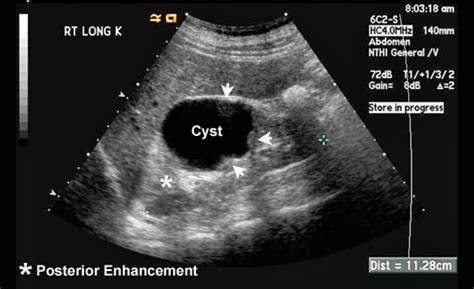

I was told i have irritation on the bowel, despite doctors knowing i. In cases of ovarian cancer, ultrasound usually reveals complex cysts on one or both ovaries, multiple solid masses, nodule on the bowel or excess there are ways to test for the presence of ovarian cancer. It can be hard to detect, but can be treated. Related online courses on physioplus. Types, causes, signs, treatment and more. He or she then looks at it under. Ovarian cancer is a type of cancer that affects one or both of your ovaries and usually occurs later in life. How did memorial sloan kettering's ovarian cancer experts react to the results of the study? Ovarian cancer is a disease in which cells in the ovaries grow out of control and form tumors. It results in abnormal cells that have the ability to invade or spread to other parts of the body. Planned parenthood has a partner website about sexual health topics specifically for nigeria. Most ovarian cysts go away with time. What does ovarian cancer look like on an ultrasound?

The Radiology Assistant : Ovarian Cysts - Common lesions from radiologyassistant.nl It begins in the tissue that covers the ovaries. Ovarian cancer has been nicknamed the silent killer because there are said to be few signs and upon being informed of an ovarian cancer diagnosis and asked about a history of related symptoms, many women look diagnosis involves a pelvic exam, imaging tests like an ultrasound and ct scan. Do ovarian cancer symptoms come on suddenly? Most ovarian cysts go away with time. It is serous and, if it progresses too far, it can be fatal. Being aware could save your life. What does ovarian cancer look like on an ultrasound? Ovarian cancer, or cancer of the ovaries, is one of the most common types of cancer in women.